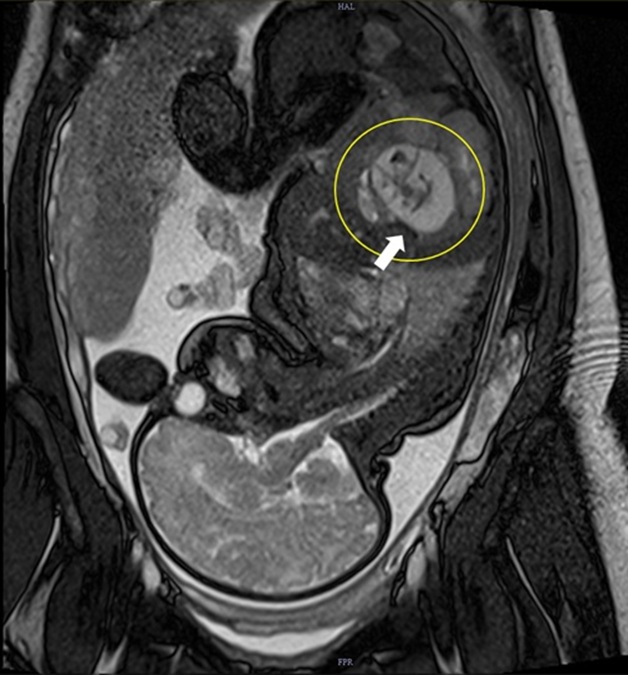

Amrita Hospital, Kochi have successfully performed a rare and delicate surgery to remove a fetus in fetu—an extremely uncommon congenital condition in which a malformed twin becomes enclosed within the body of its normal twin during early embryonic development. Fewer than 1 in 5,00,000 births present this anomaly worldwide, making this case a remarkable medical milestone.

The condition was first diagnosed at the antenatal scanning done by Dr Vivek Krishnan, Additional Professor, Dr. Dhanya Keezhatoor and Dr. Sruthi Soman, Assistant Professors from the department of fetal care. Advanced prenatal imaging revealed an abnormal mass, prompting close monitoring and expert evaluation. Antenatal scans play a crucial role in identifying such complex conditions early, enabling timely intervention after birth.

After delivery, further imaging confirmed the presence of fetus in fetu—a non-viable twin entrapped inside the abdomen of the surviving infant. At just two months old, the baby girl underwent a complex open surgery at Amrita Hospital to remove the malformed fetus, which weighed 48.7 grams.